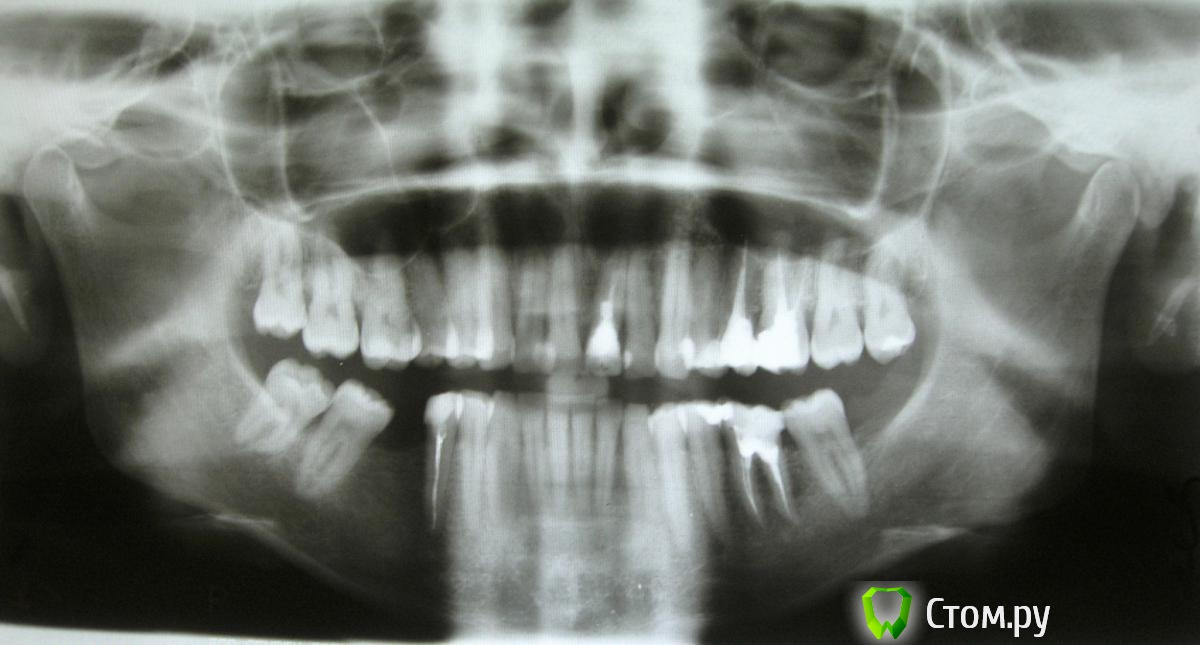

rbc-rbc Опубликовано 2 апреля, 2014 Поделиться Опубликовано 2 апреля, 2014 Добрый вечер.Образовалось два места, где была нужна имплантация. Шестерка нижняя правая (имплантат поставлен) и шестерка верхняя левая сторона (в планах установить имплантат).1. На нижней челюсти стоит имплант Лико, диаметр 3,6 мм, длина 13 мм. Прилагаю ортопантомограмму (1) (вид до имплантации, зуба нет с 1995 года), прицельный снимок (2) (день установки имплантата) и фотографию полости рта после установки формирователя десны (3).Все ли в порядке в плане положения имплантата, размеров, выбора формирователя десны, создания условий для протезирования? Ортопед, как я поняла, обтачивать соседние зубы не намерен. Не стоит ли сточить нависающий край сильно наклоненной семерки?2. В левой области верхней челюсти хирург намерен делать закрытый синус-лифтинг и ставить имплант диаметром 4 мм. Длина 8-10 мм - в зависимости от того, как позволит наращивание кости в высоту в области гайморовой пазухи. Смущает выбор имплантата небольшого диаметра для такого зуба. Прилагаю скрин снимка (4). Эту шестерку удалили 21.06.13, так как она не подлежала лечению. Со щечной стороны после удаления образовалась выемка. Доктор молчит по поводу утолщения, наращивания кости в месте имплантации, видимо, не считает нужным увеличивать ее объем.Что в таком случае предпринять?Какого диаметра имплантат будет оптимален в этом месте?Стоит ли наращивать кость, заполняя выемку сбоку? Если да, то - пересадка собственной кости или искусственные материалы?Спасибо большое за уделенное внимание и помощь.Примечание:снимок 1 - 31.05.10снимок 2 - 06.09.13снимок 3 - 27.03.14снимок 4 - 25.11.13 Ссылка на комментарий